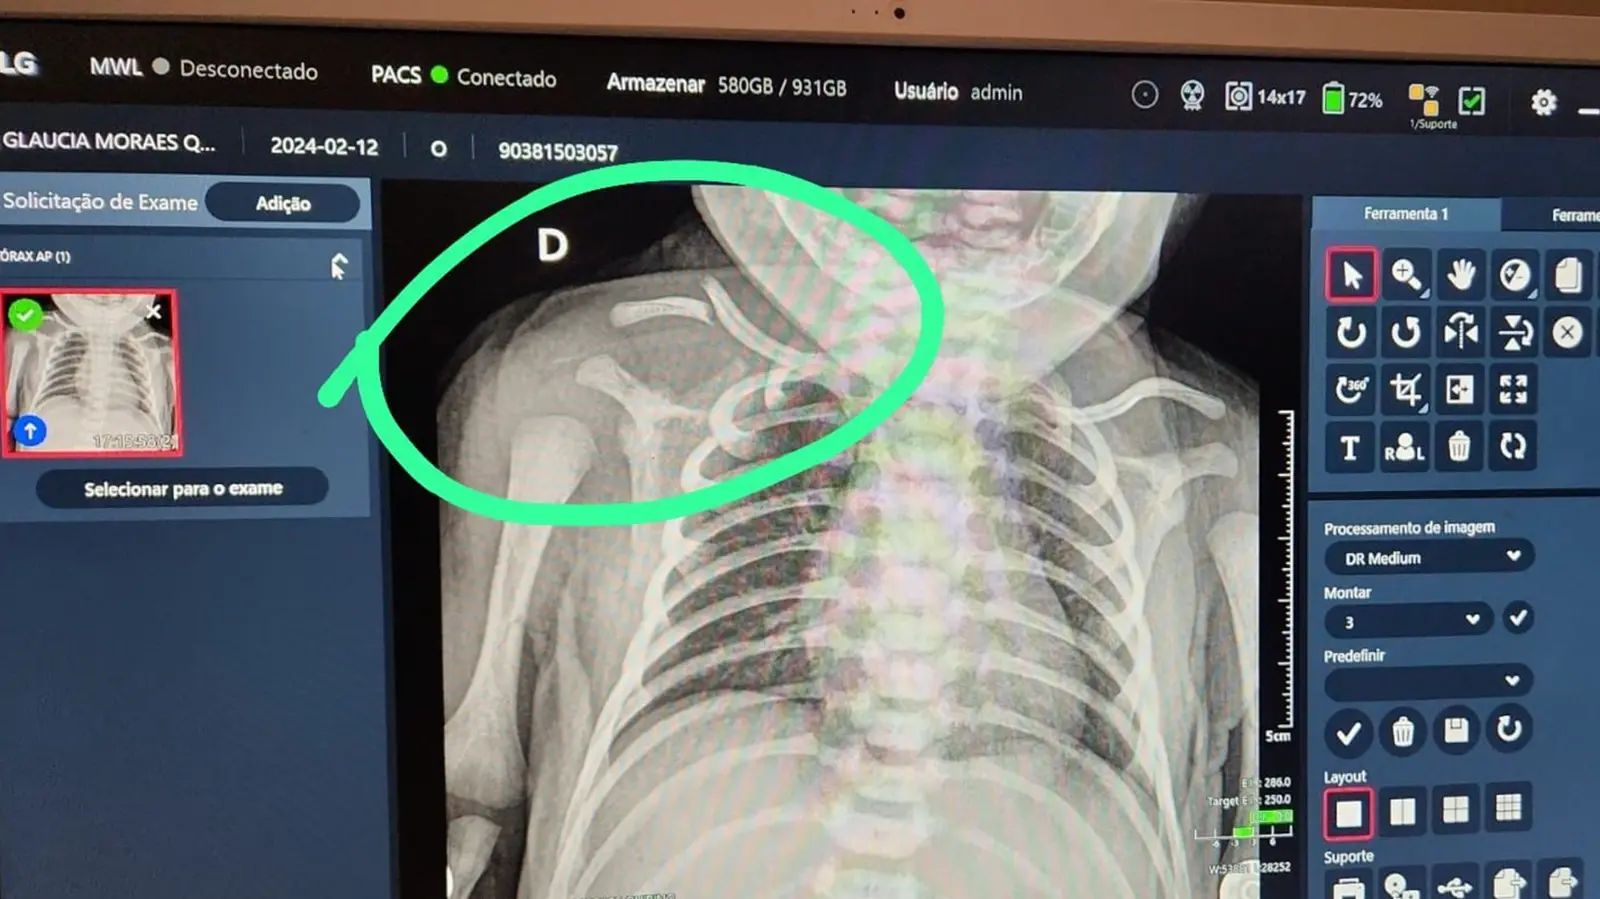

Ainda de acordo com a avó, no HIMABA, o bebê foi prontamente atendido, submetido a exames de raio-X e recebeu um encaminhamento para acompanhamento ambulatorial. A família, que mora na cidade de Serra, precisou recorrer a serviços de transporte por aplicativo para realizar o deslocamento até Vila Velha e retornar para casa.